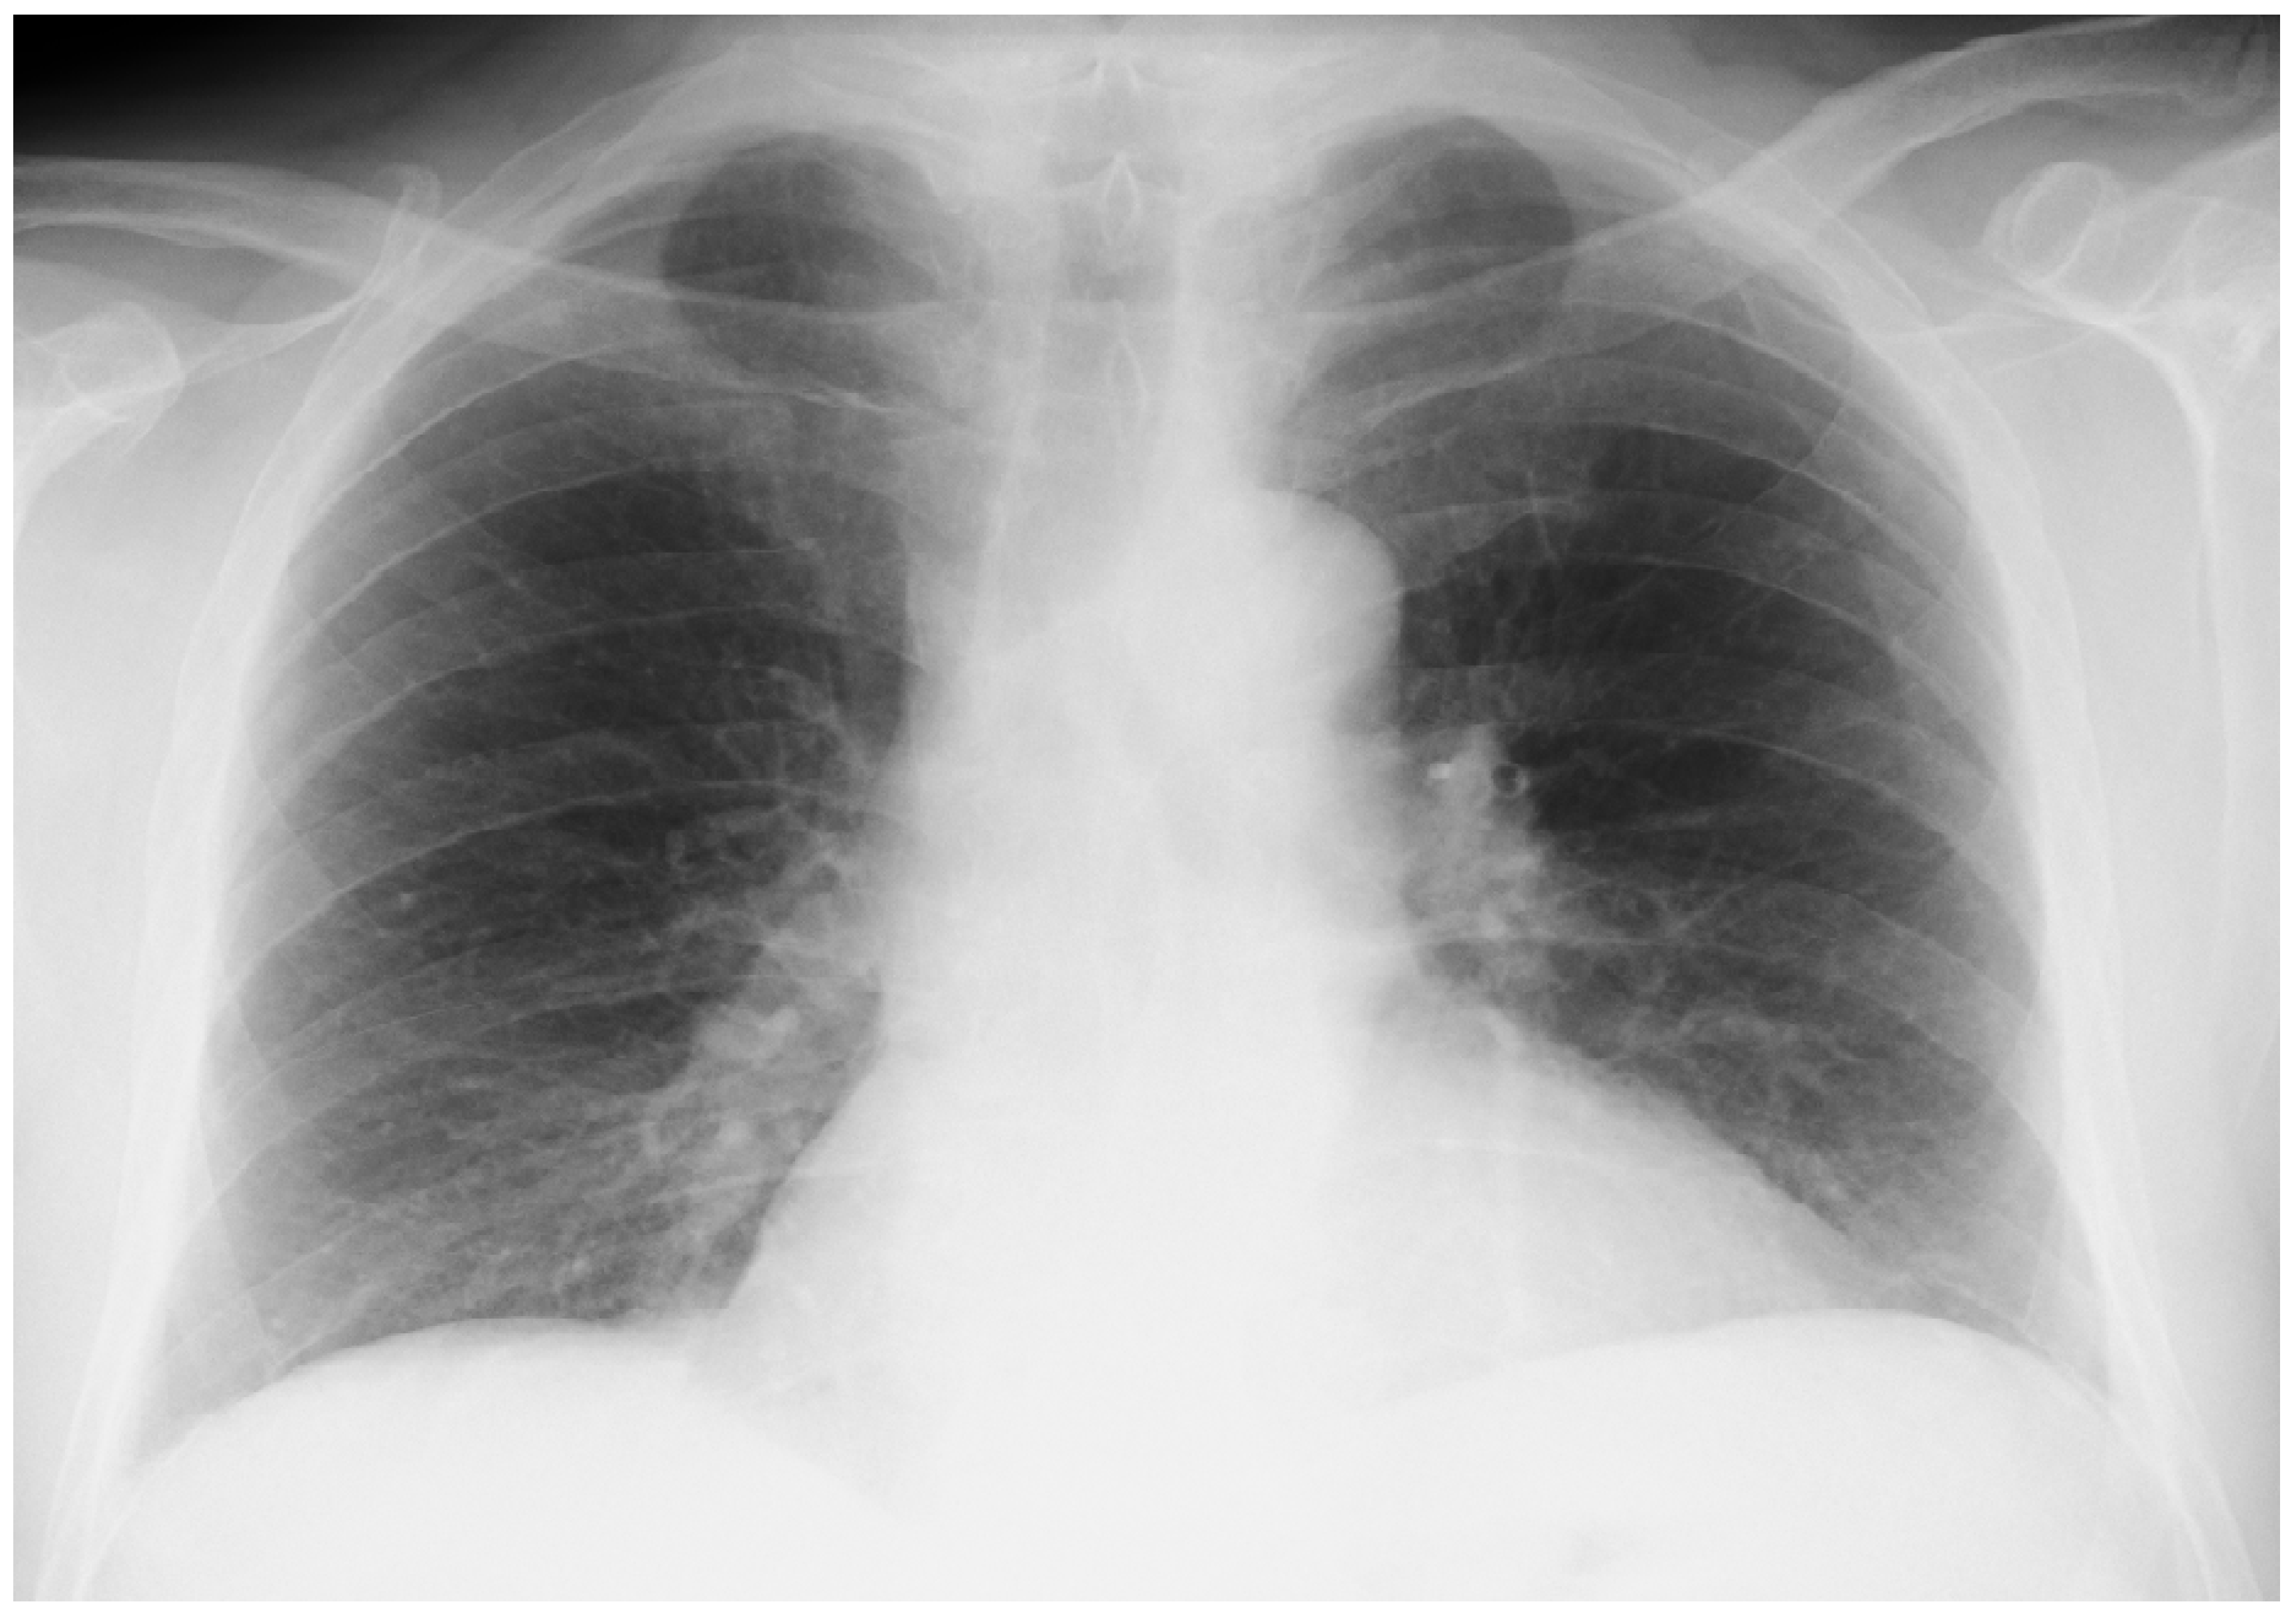

Onset of the Disease

An Accidental Overdose of Colchicine Results in Immediate Recovery of the Patient